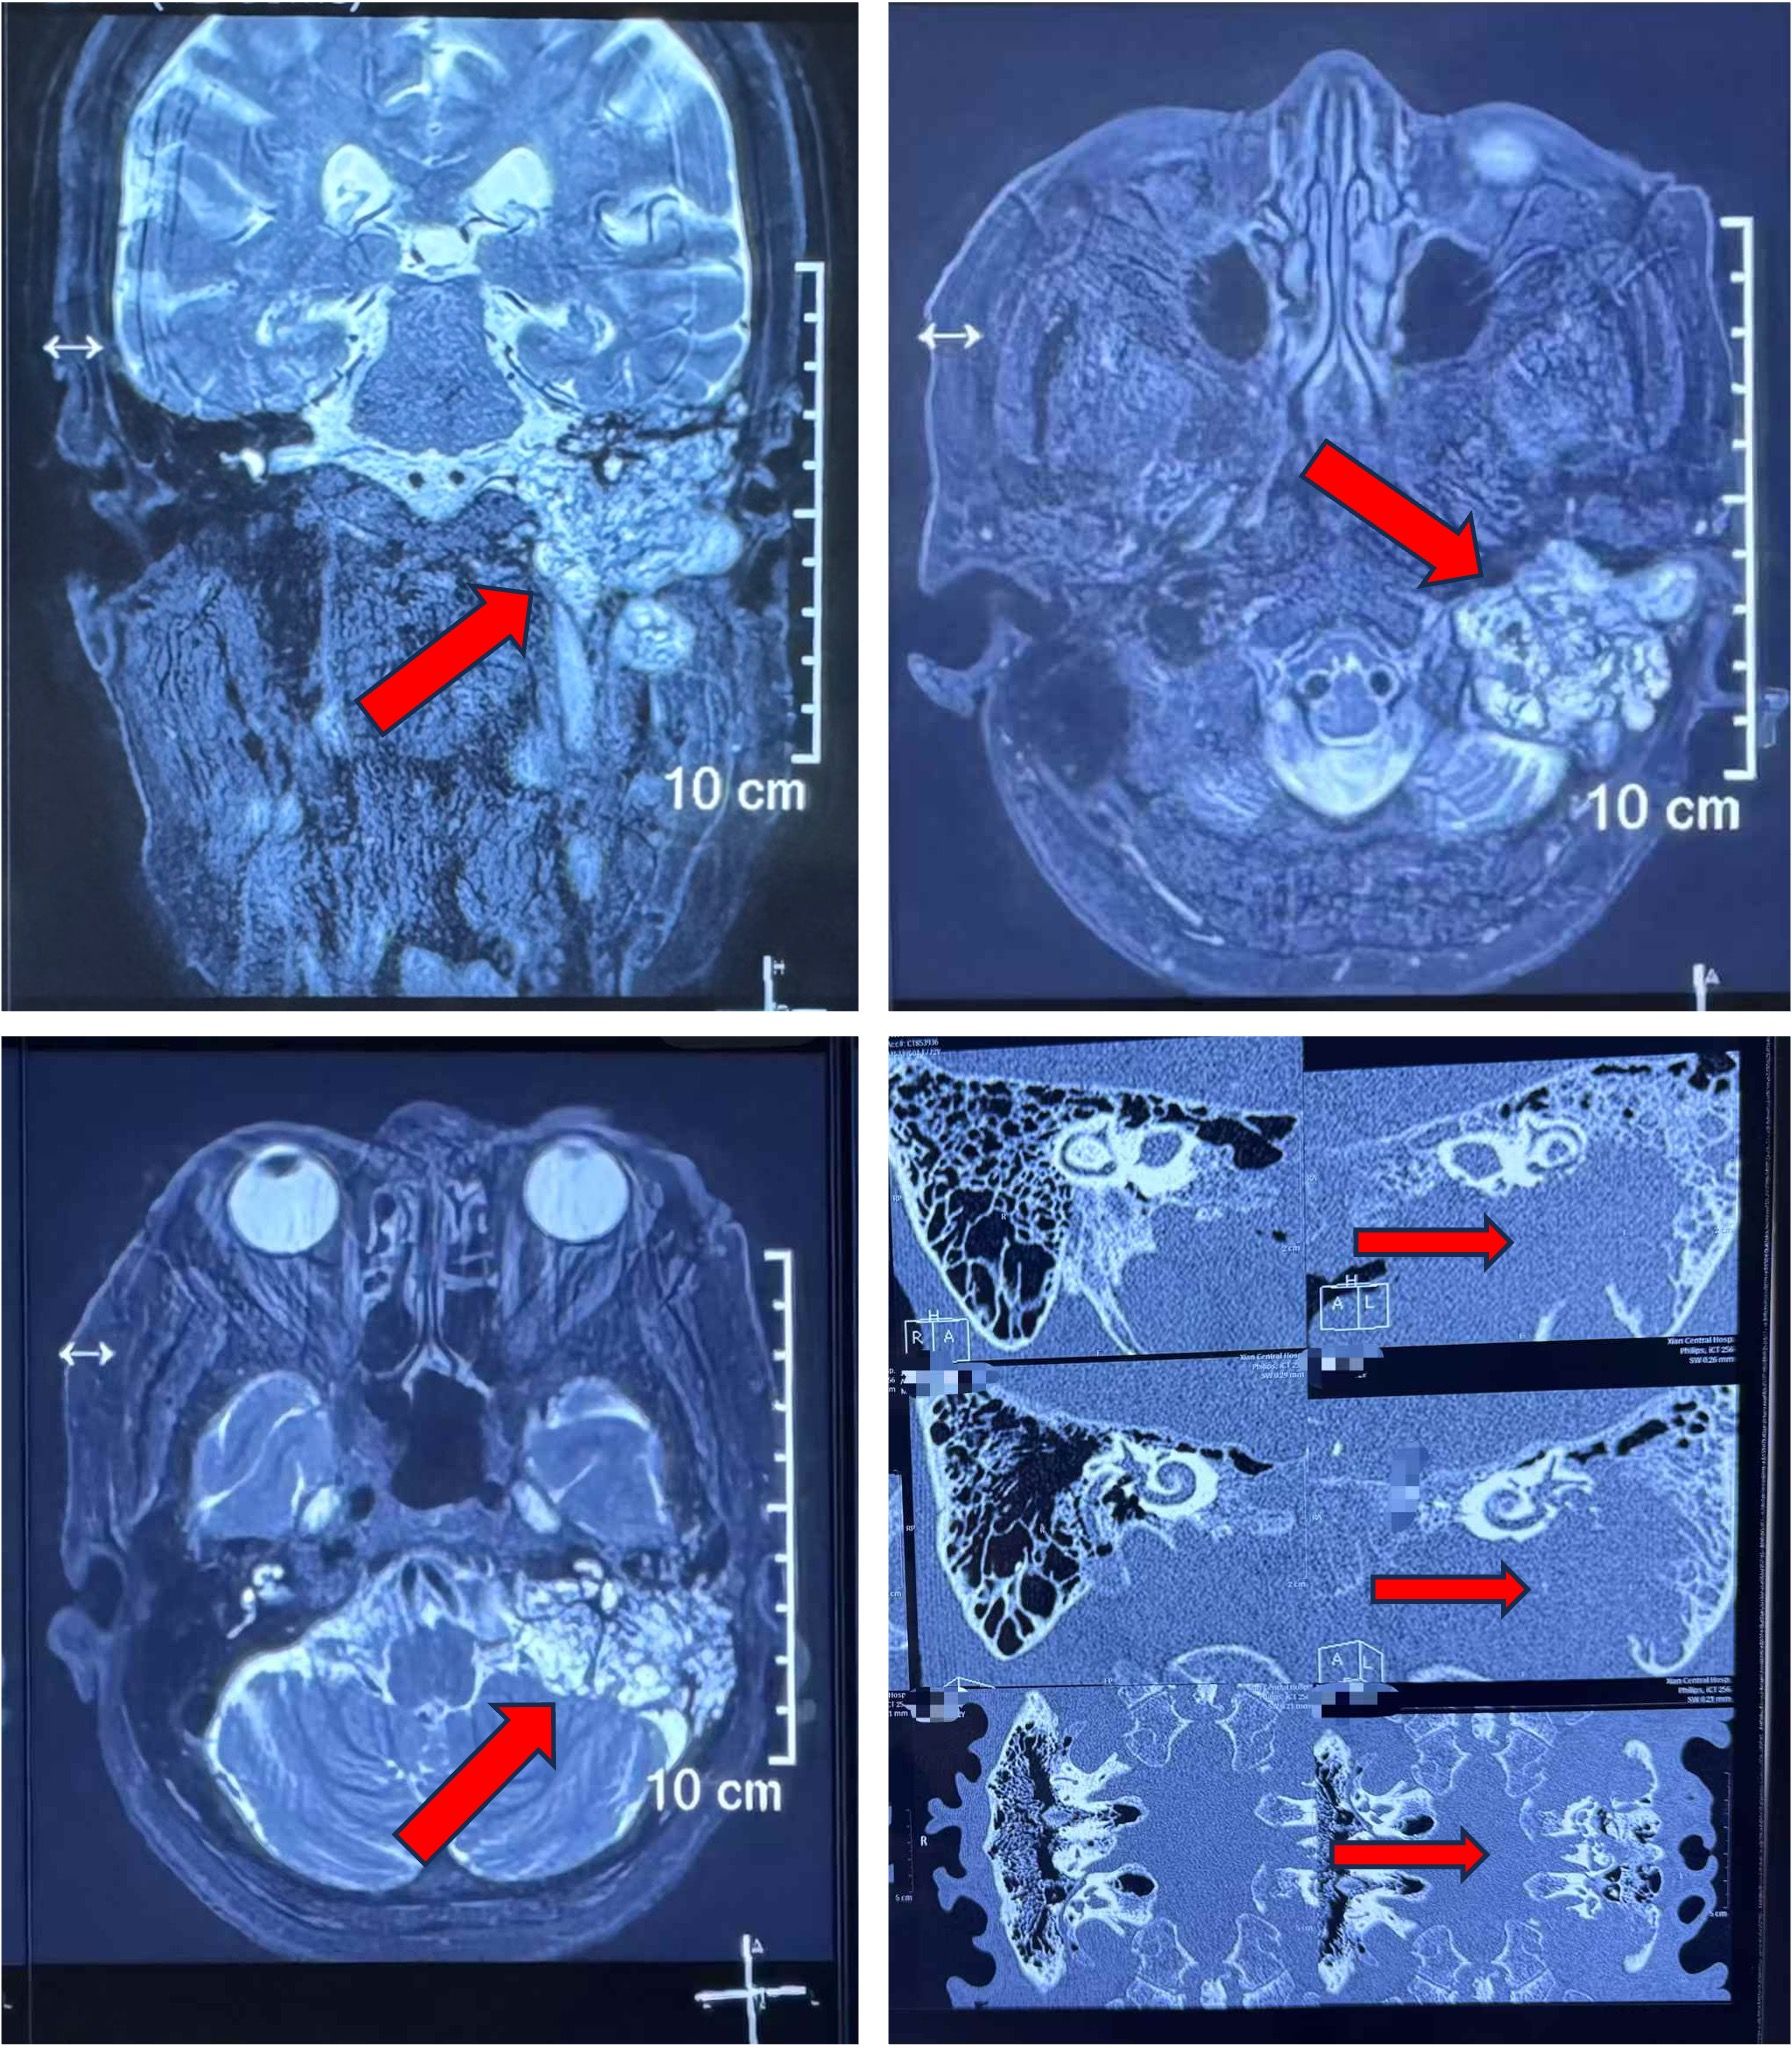

耳鼻喉迅速给患者开辟绿色通道及时收住入院,经过检查确诊为“左侧面神经瘤”。但由于患者病程长,影像学显示患者面神经瘤侵犯范围特别广泛,自面神经内听道至面神经腮腺段全部侵犯,且已压迫至小脑,目前医学文献尚无报道有如此巨大肿瘤患者。

耳鼻喉科迅速对患者进行全面评估,任晓勇主任、孙斌副主任、胡娟副主任积极组织科内病案讨论,并由麻醉科雷晓鸣主任、神经外科王睿智教授、肿瘤科昝英教授参与院内MDT讨论充分评估麻醉手术风险,认为该手术风险极大。由于患者肿瘤已破坏颅底及中颅窝骨质结构,颈内动脉、颈静脉球、乙状窦等大血管表面也均有骨质破坏及肿瘤粘连,术前进行了积极备血、颅内组织损伤修复等预案。

上报医务科后,耳鼻喉科为患者进行了面神经肿瘤切除术。手术由张滟副主任医师主刀,胡娟副研究员、麻醉师李伟教授、高明姬护士及手术室各方通力协作,历经10小时,将肿瘤安全切除。由于肿瘤质脆易出血,传统夹取切除不容易辨认结构并容易造成大量出血损伤,手术医生采用常规切除加盐水棉片止血剥离等方式仔细操作,最终在切除肿瘤的同时,保证了脑膜、颈动脉管、颈静脉球等结构的完整无损。术中未输血,术后患者未出现颅脑损伤情况,安全返回普通病房。经过围手术期的精心护理,术后十天患者出院,出院时患者已可自行行走、起居饮食逐渐恢复正常。

面神经肿瘤为侧颅底少见肿瘤,在周围性面瘫人群发病率约为5%,渐进和反复发作的面瘫是常见临床表现,手术是主要治疗方式。肿瘤可波及面神经自内听道至颞骨外段五个节段中的任意节段,但本例波及上述面神经全部节段的特大肿瘤目前文献尚无报道,且患者已出现肿瘤压迫脑组织及重要血管神经等表现,若不及时救治可造成严重后果。